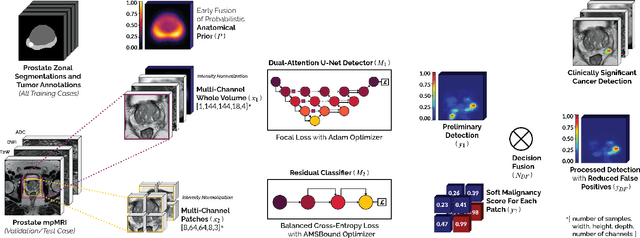

End-to-end Prostate Cancer Detection in bpMRI via 3D CNNs: Effect of Attention Mechanisms, Clinical Priori and Decoupled False Positive Reduction

We present a novel multi-stage 3D computer-aided detection and diagnosis (CAD) model for automated localization of clinically significant prostate cancer (csPCa) in bi-parametric MR imaging (bpMRI). Deep attention mechanisms drive its detection network, targeting multi-resolution, salient structures and highly discriminative feature dimensions, in order to accurately identify csPCa lesions from indolent cancer and the wide range of benign pathology that can afflict the prostate gland. In parallel, a decoupled residual classifier is used to achieve consistent false positive reduction, without sacrificing high sensitivity or computational efficiency. Furthermore, a probabilistic anatomical prior, which captures the spatial prevalence of csPCa as well as its zonal distinction, is computed and encoded into the CNN architecture to guide model generalization with domain-specific clinical knowledge. For 486 institutional testing scans, the 3D CAD system achieves $83.69\pm5.22\%$ and $93.19\pm2.96\%$ detection sensitivity at 0.50 and 1.46 false positive(s) per patient, respectively, along with $0.882$ AUROC in patient-based diagnosis $-$significantly outperforming four state-of-the-art baseline architectures (U-SEResNet, UNet++, nnU-Net, Attention U-Net) from recent literature. For 296 external testing scans, the ensembled CAD system shares moderate agreement with a consensus of expert radiologists ($76.69\%$; $kappa=0.511$) and independent pathologists ($81.08\%$; $kappa=0.559$); demonstrating strong generalization to histologically-confirmed malignancies, despite using 1950 training-validation cases with radiologically-estimated annotations only.